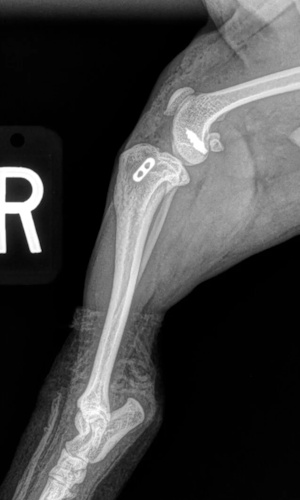

Pre-Surgical Radiographs

Orthogonal radiographs of both stifles are obtained and assessed. In the majority of cases, an effusion is visible within the stifle that demonstrates inflammation and pathology of the joint. The joint is assessed for other diseases such as osteochondritis dissecans (OCD), or neoplasia (cancer). Chronic cruciate injuries or those with concurrent meniscal damage tend to have an increased amount of degenerate changes visible on the radiographs.

Post Surgical Radiographs

While the patient is still anesthetized, the patient is taken into radiology for post-surgery radiographs (X-rays). The radiographs are assessed to ensure the apparatus FASTak screw and toggle are appropriately positioned.

While the patient is still anesthetized, the patient is taken into radiology for post-surgery radiographs (X-rays). The radiographs are assessed to measure the new tibial plateau angle. We are aiming for 5-6 degrees relative to the long axis of the tibia. The apparatus (plate and screws) are assessed for size and appropriate position.